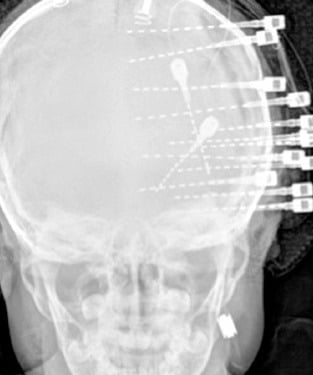

Funktionelle und Epilepsiechirurgie

Chirurgie für fokale Epilepsien

Interdisziplinäre Zusammenarbeit mit der Universitätsklinik für Neurologie